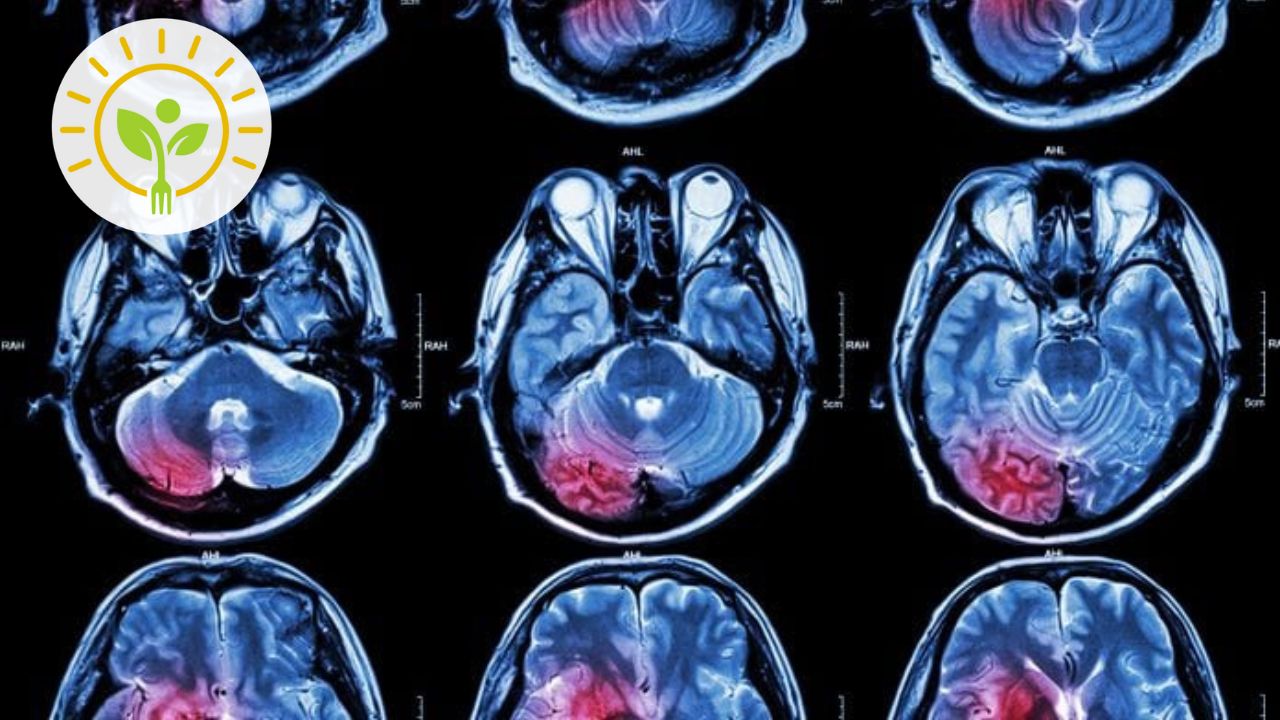

Fisiopatologia da doença de Alzheimer